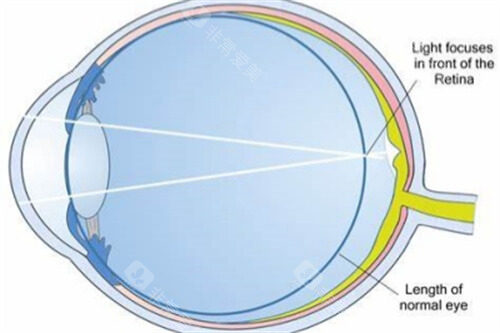

术前:采用Pentacam三维眼前节分析仪进行角膜生物力学评估

采用Corvis ST角膜生物力学分析仪,比较准测量角膜抗变形能力。